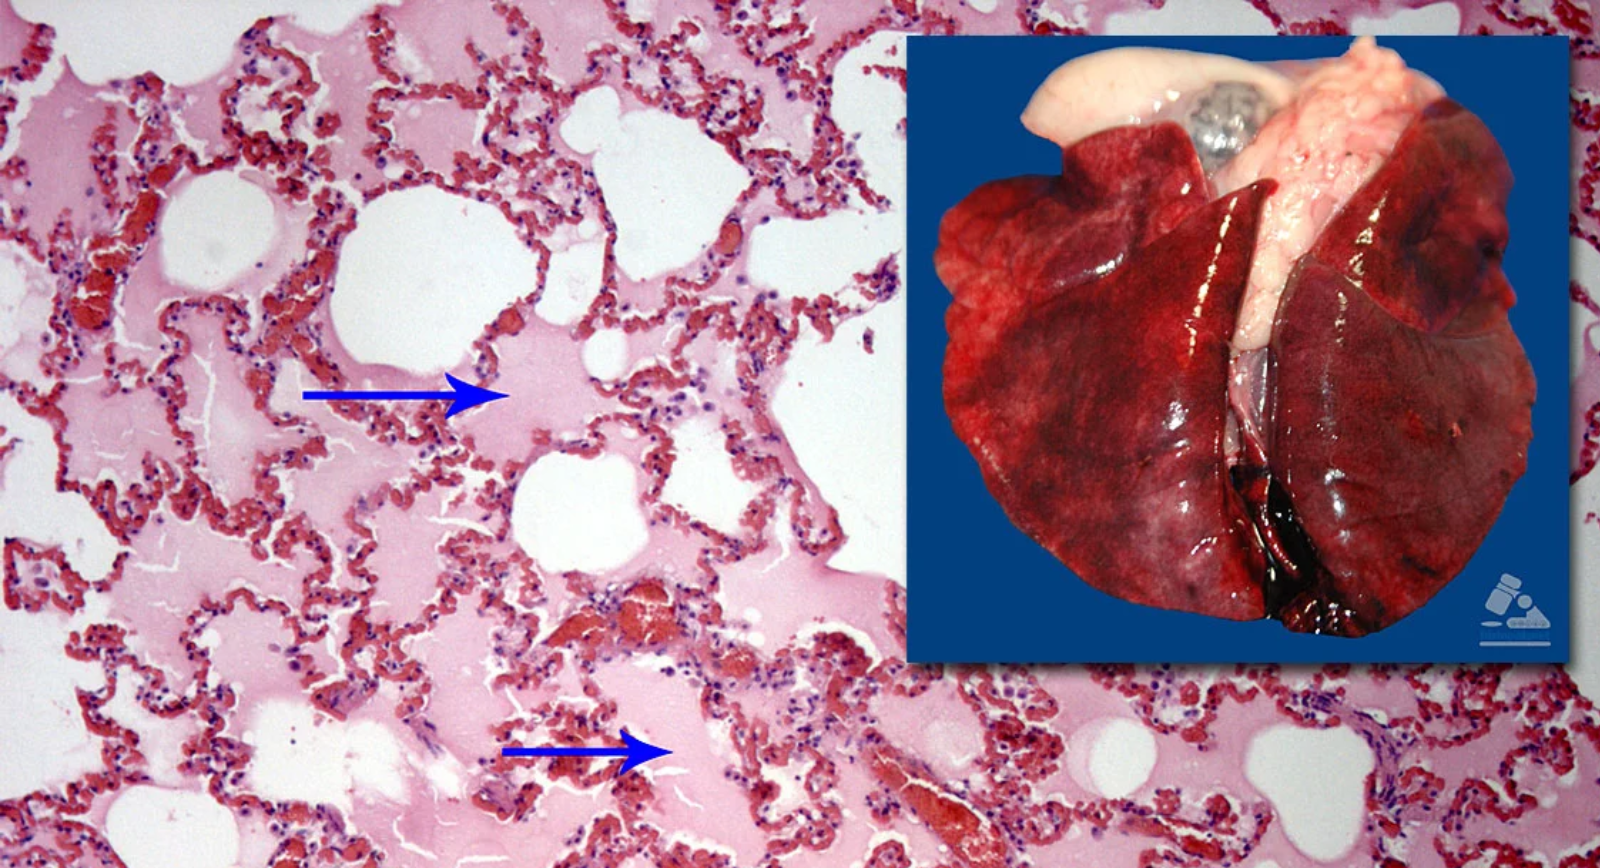

Fig. 6. Parénquima pulmonar. Las flechas señalan un material rosado dentro de los alveolos (edema pulmonar). En la parte superior el pulmón, con un aspecto rojizo difuso.